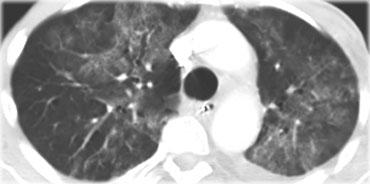

Đây là một trường hợp sarcoidosis phế nang.

Hình ảnh trông giống như tăng tỷ trọng dạng kính mờ, nhưng khi quan sát kỹ hơn có thể nhận thấy rằng sự tăng tỷ trọng này là kết quả của nhiều nốt nhỏ tập hợp lại.

Cũng lưu ý hạch to rốn phổi.